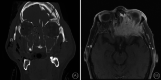

Methods: Two latex-injected cadaveric specimens were utilized to perform surgical dissections to demonstrate different approaches to the MS. The procedures were documented with macroscopic images and endoscopic pictures.

Results: Dissections were performed to approach the MS medially (endoscopic maxillary antrostomy and ethmoidectomy), anteriorly (Caldwell-Luc), superiorly (transconjunctival/transorbital approach), inferiorly (transpalatal approach), and posterolaterally (preauricular hemicoronal approach).